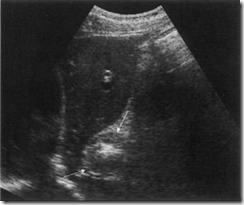

Ultrasound images of Normal oesophagus between the aorta and the left lobe of the liver—thin, hypoechoic walls with a hyperechoic lumen due to the presence of air.

ultrasound images of Thickened walls of the oesophagus in a carcinoma involving the lower oesophagus.